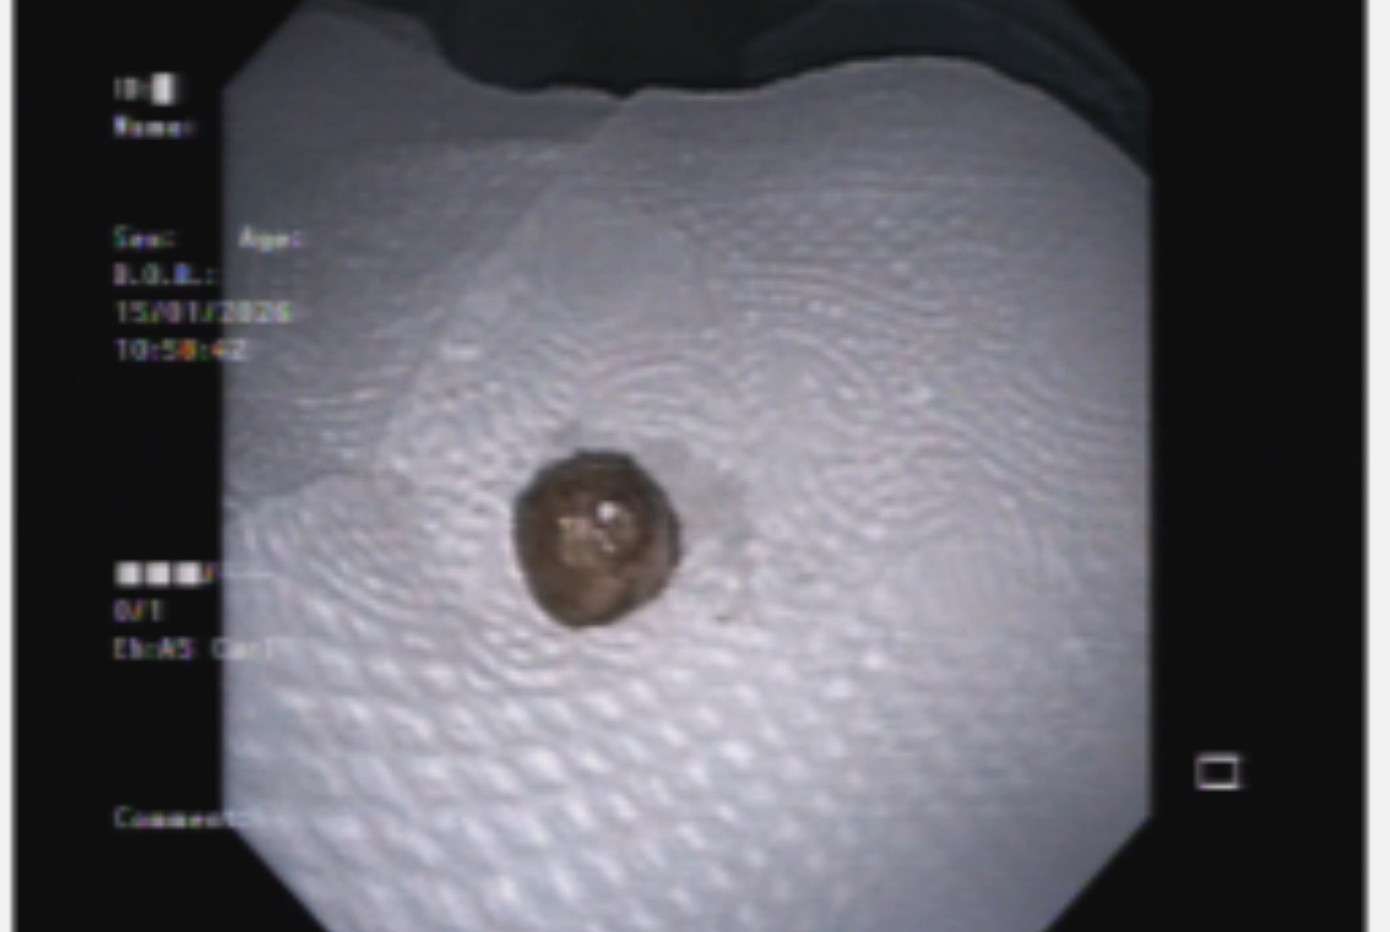

Bệnh nhân được chỉ định nội soi phế quản cấp cứu. Quá trình nội soi phát hiện dị vật lấp kín hoàn toàn phế quản gốc trái. Dị vật có tính chất mềm, dễ vỡ, tiềm ẩn nguy cơ rơi xuống các nhánh phế quản nhỏ nếu thao tác không cẩn trọng. Nhờ sử dụng các thiết bị nội soi chuyên dụng và sự phối hợp chặt chẽ giữa ê-kíp nội soi hô hấp và tiêu hóa, dị vật đã được lấy ra an toàn.

Dị vật là viên thuốc có dạng tròn, mềm, màu vàng, kích thước khoảng 10x10mm. Khai thác kỹ tiền sử ghi nhận bệnh nhân từng bị sặc khi uống một loại thuốc có hình dạng tương tự.

Sặc một viên thuốc, cụ bà xẹp toàn bộ phổi trái- Ảnh 2.

Dị vật được lấy ra.